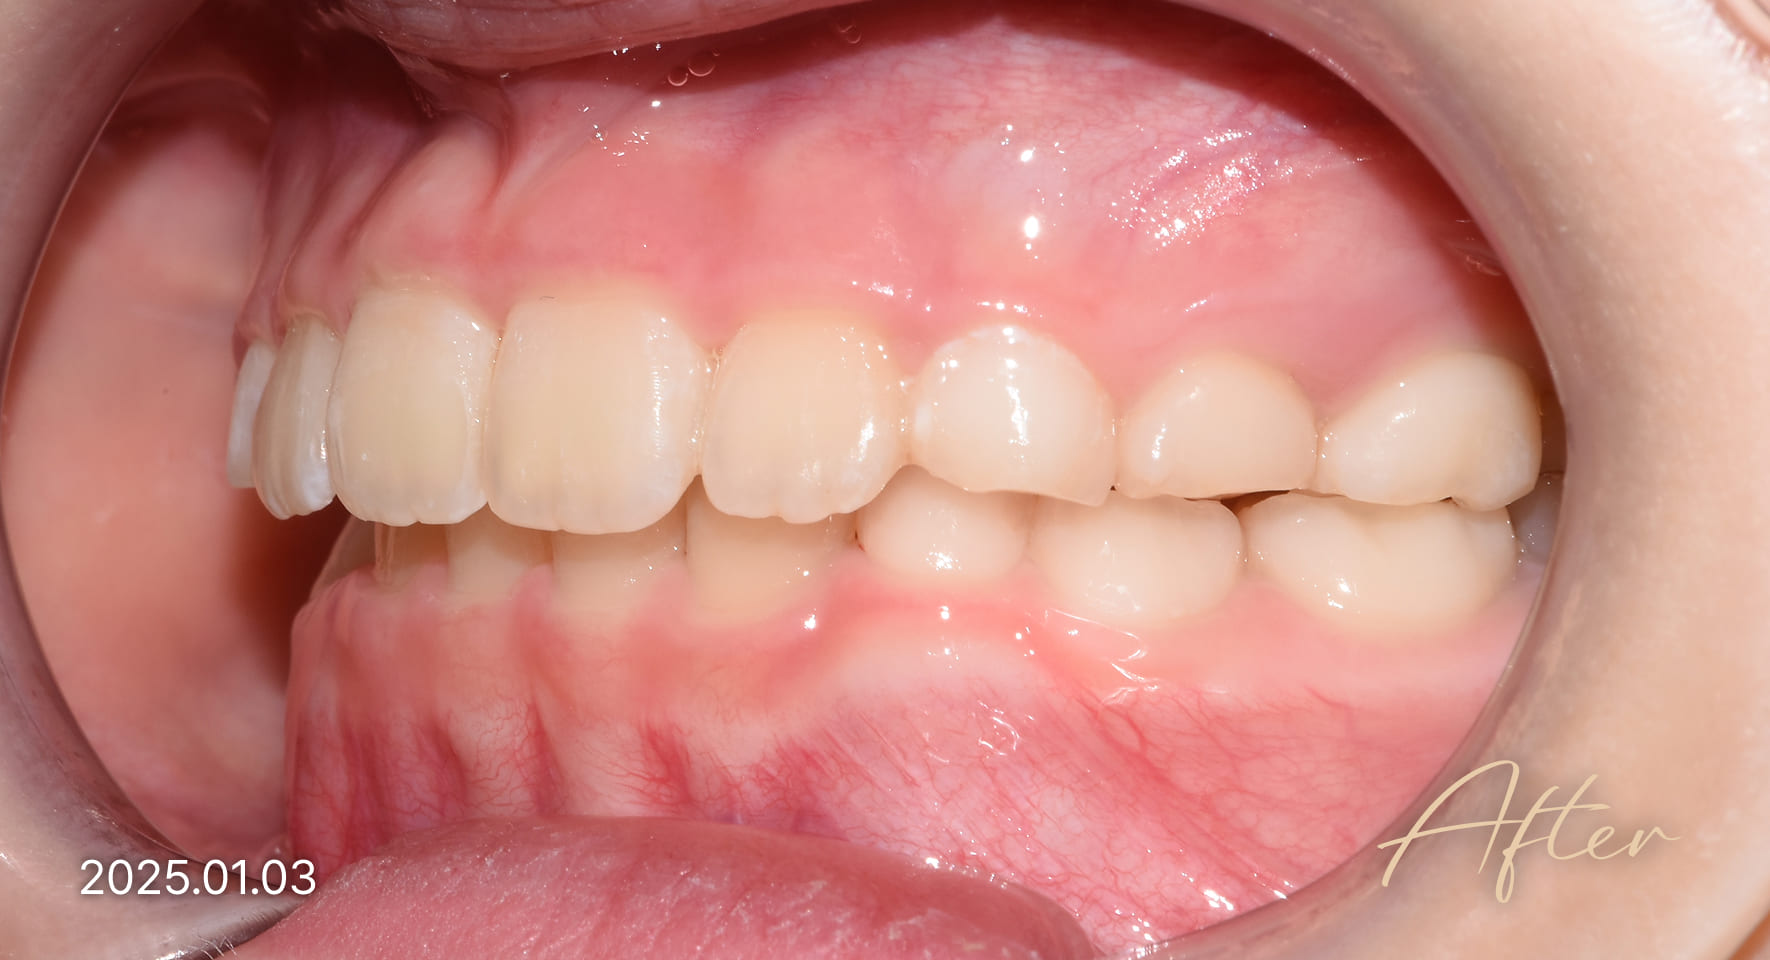

성장기 교정 치료사례

본 사진은 진심을담은치과교정과 치과의원에서

치료한 환자의 동일 인물 전·후 사진입니다.

개인의 구강 상태 및 관리 방법에 따라 통증 및 잇몸 염증,

턱관절 불편감 등의 부작용이 발생할 수 있습니다.

치료 전 치료 후